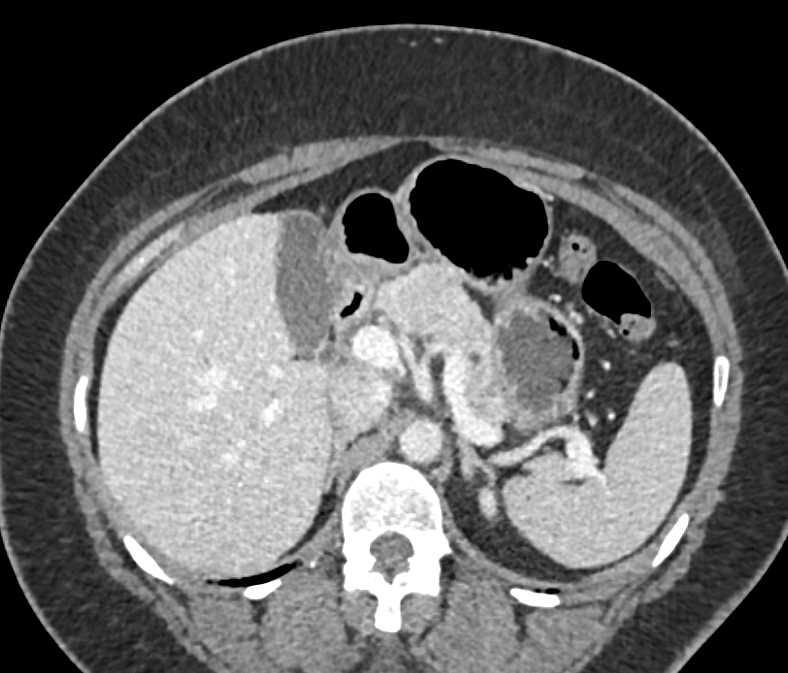

Neuroendocrine Tumor Body of Pancreas